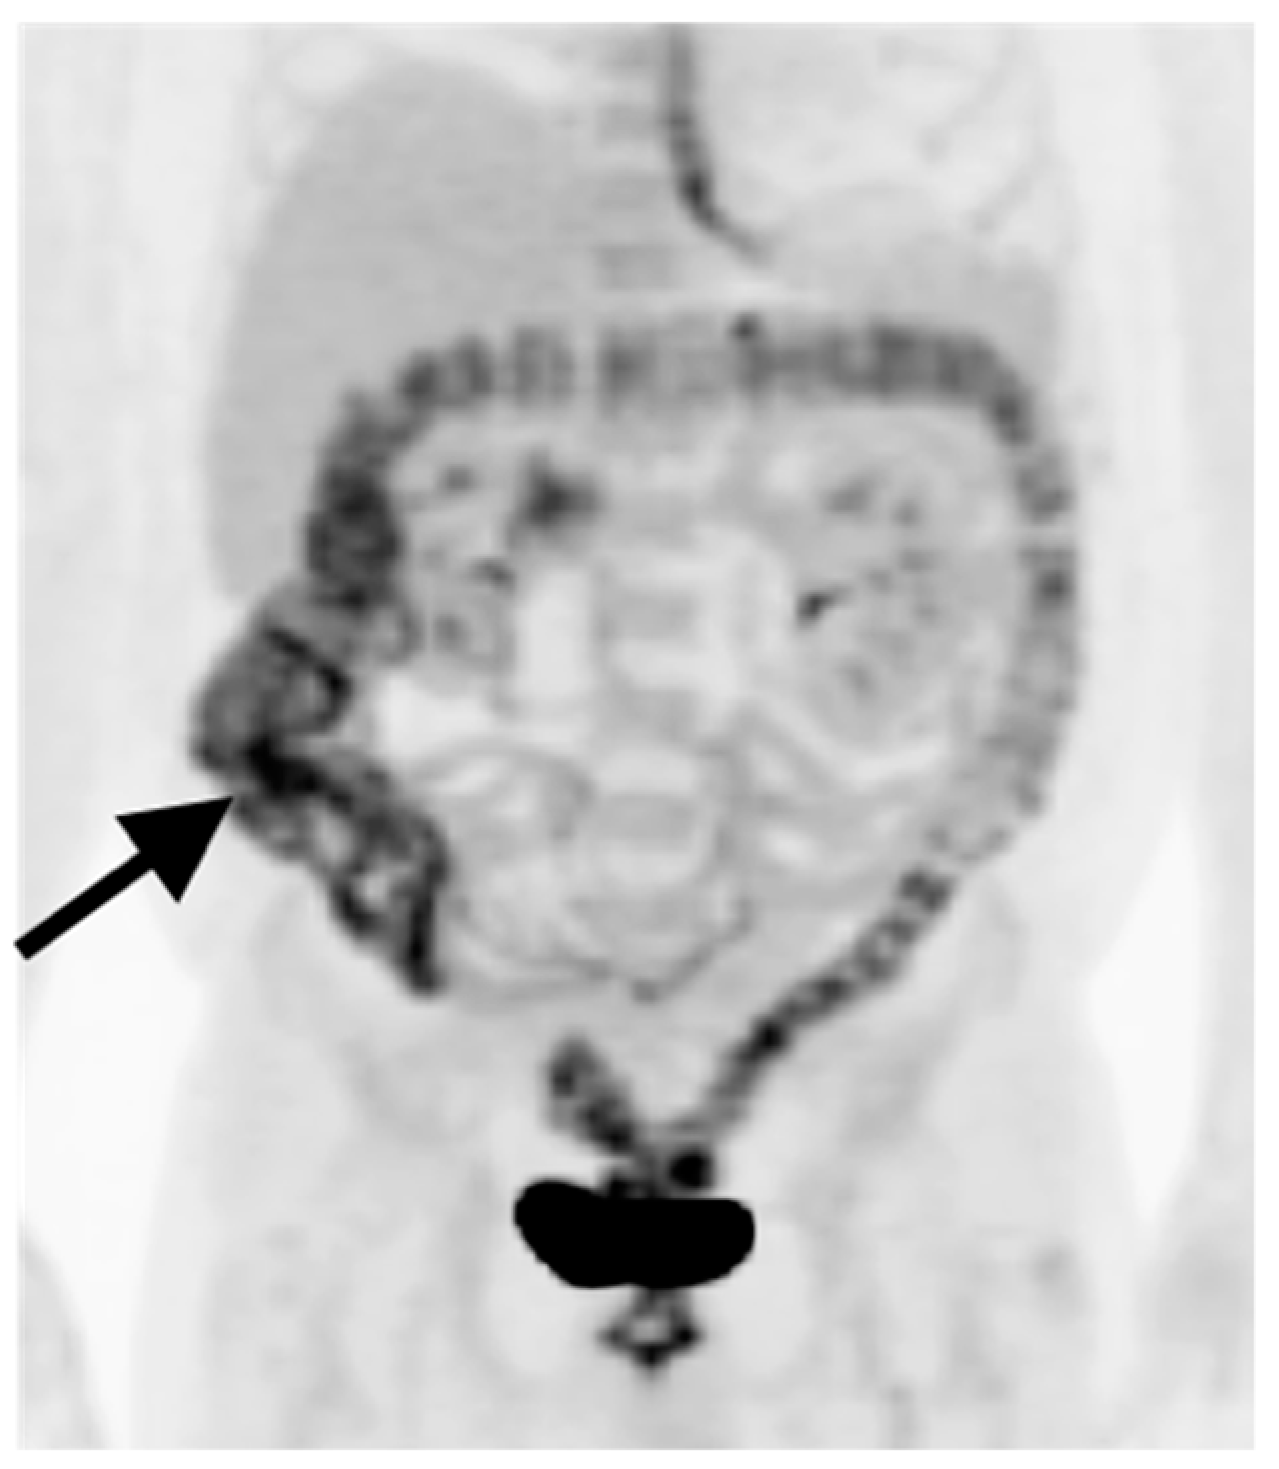

9. Bowel Adenocarcinoma: Colon, Rectum, Small Bowel